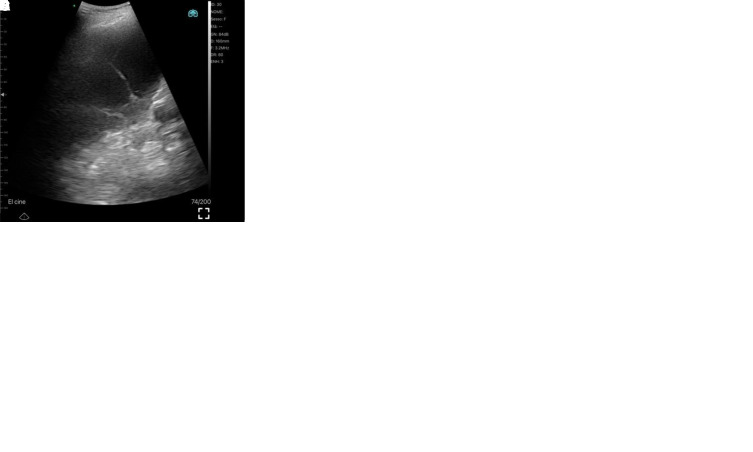

Abstract Image